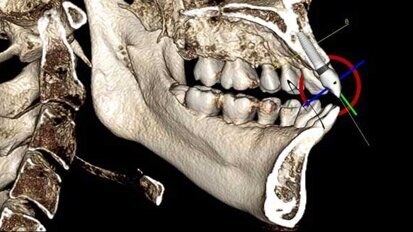

3D imaging: Increasing implant accuracy

Implants are making news on a global scale. According to The Wall Street Journal’s Market Watch, the implant market “is mainly driven by the ...